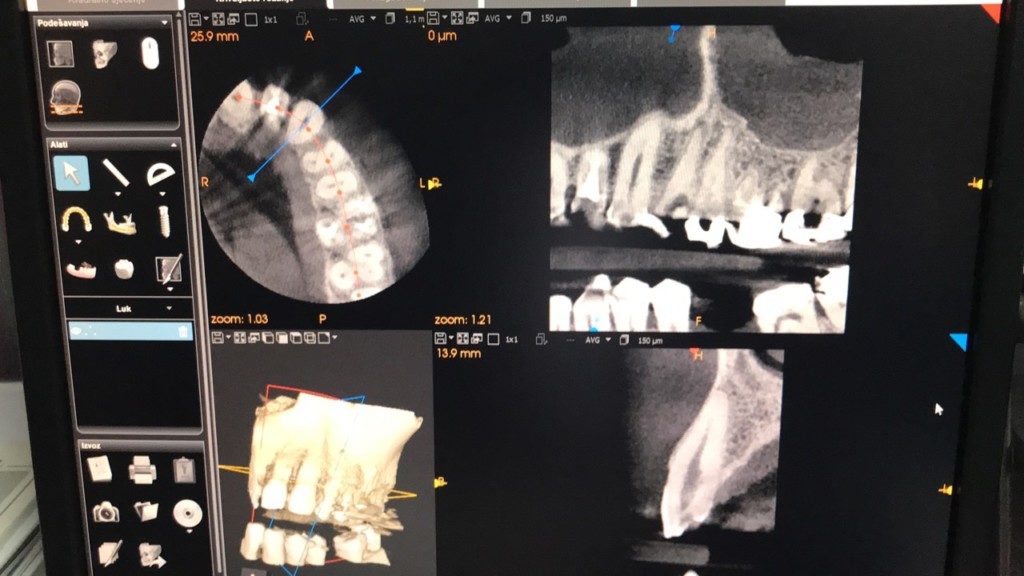

Ovaj jedinstveni uređaj, koji svojom multifunkcionalnošću i kvalitetom snimanja nudi vrhunske rezultate, isporučili smo i montirali protekle sedmice u njihovoj ordinaciji u Sarajevu (Branislava Nušića 166). Kako izgleda pogledajte kroz par slika.

Carestream CS 8100 3D je vrhunsko “sve-u-jednom” rješenje, te pokriva širok raspon primjena, jedinica je idealna za svakodnevnu uporabu i nudi najvišu kvalitetu slike – istinski stavljajući moć 3D tehnologije za snimanje na dohvat ruke. Više o samoj jedinici pogledajte u videu ispod: